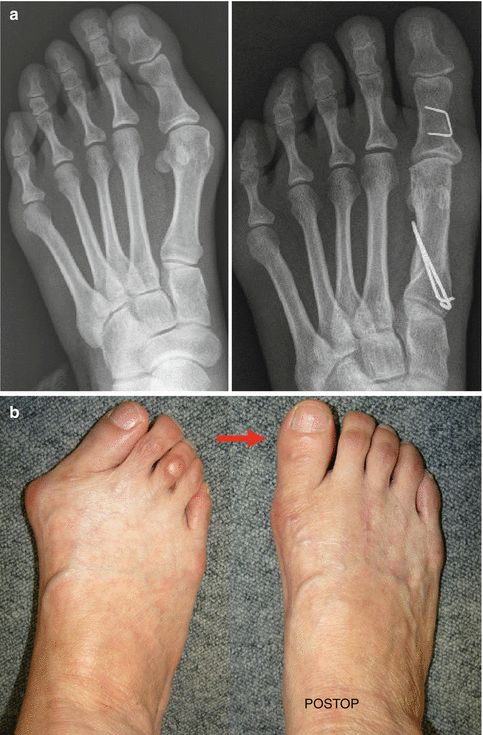

对于脚本身,踮脚姿势增加前脚掌压力(特别是拇趾周围),加上很多尖鞋头挤住脚趾,会改变足弓高度,使拇外翻风险升高1~2倍,还可能导致足底筋膜炎及骨骼变形。

▲左侧为拇外翻X线片及足部照片,右侧为术后丨参考文献[10]